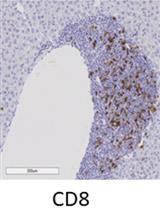

Immunology

Immunohistochemistry of Immune Cells and Cells Bound to in vivo Administered Antibodies in Liver, Lung, Pancreas, and Colon of B6/lpr Mice

Employing a novel mouse model of immune related adverse events (irAEs) induced by combination of anti-PD1 and anti-CTLA-4 antibodies, we visualized immune infiltration into the liver, lung, pancreas, and colon. Here, we describe the avidin-biotin conjugate (ABC) method used to stain T cells (CD4 and CD8), B cells (CD19), macrophages (F4/80), and cells bound by the in vivo administered rat anti-mouse antibodies for chromogenic immunohistochemistry (IHC). Using a biotinylated goat anti-rat antibody, we detected the localization of cells bound to the in vivo antibodies for PD-1 and CTLA-4. IHC has advantages over other techniques, namely antibody availability, resistance to photobleaching, and greater sensitivity. Additionally, detection and localization of in vivo antibodies can be used in mice models to infer their therapeutic efficacy, stability, and function.Graphical abstract: